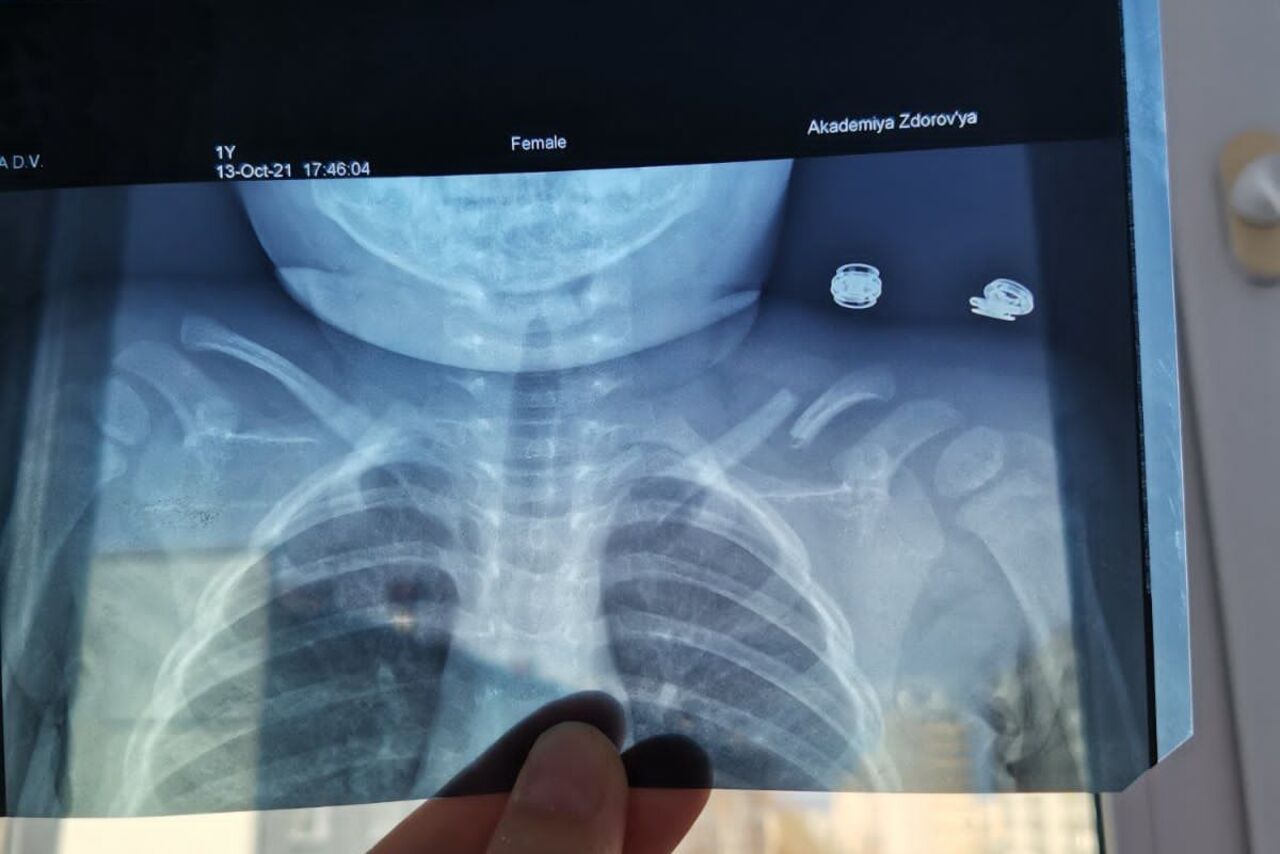

релом Ключицы У Ребенка Фото

Перелом Ключицы У Ребенка Фото 111 фотографий